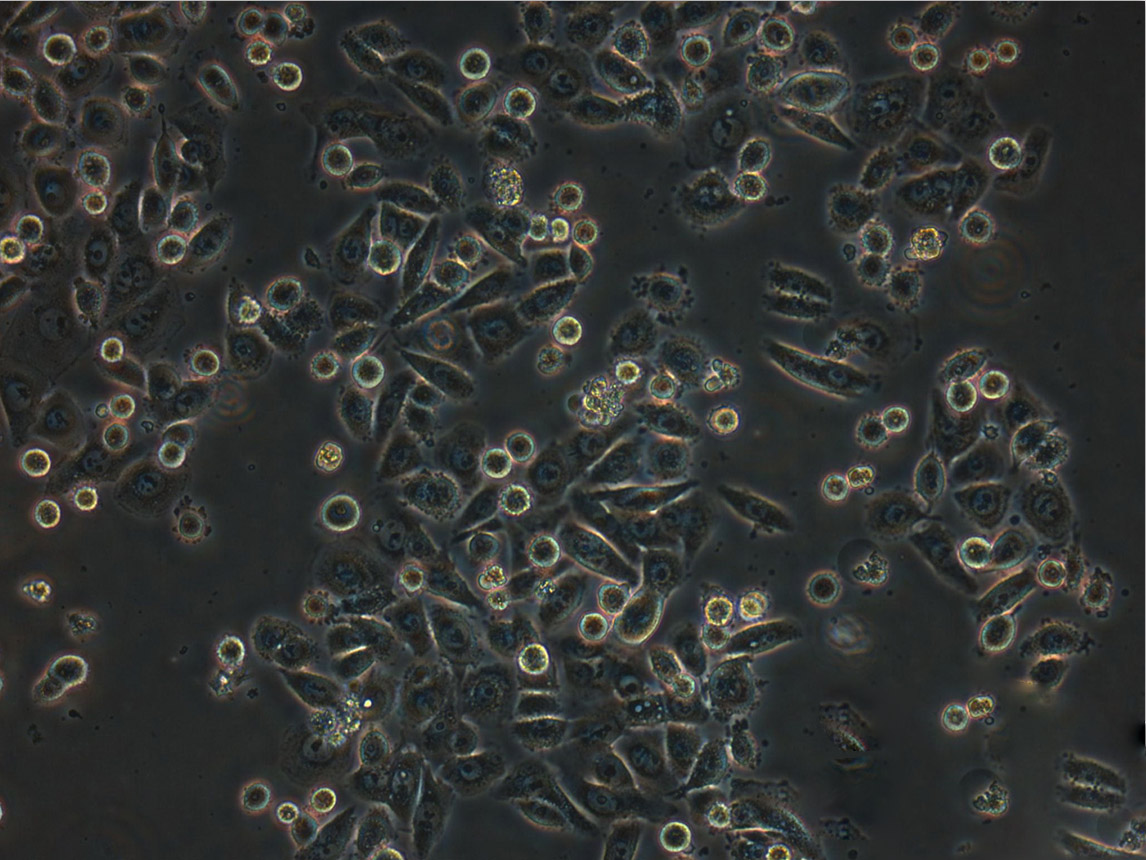

细胞形态:上皮细胞样

细胞生长:贴壁

细胞背景资料:这株细胞是从小肠肠系膜转移灶的细胞中建立的。 据报道,它含有完整的HPV-16(每个细胞大约600个拷贝)和HPV-18相关序列。

细胞生长特性:贴壁生长